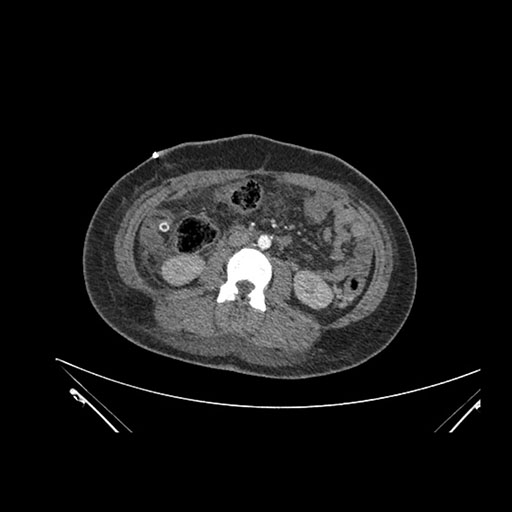

Imaging Analysis

Look through the patient's CT scan to identify any areas of concern for the necessary procedure.

Axial Arterial

Based on initial findings, which issue(s) would you be most concerned about?